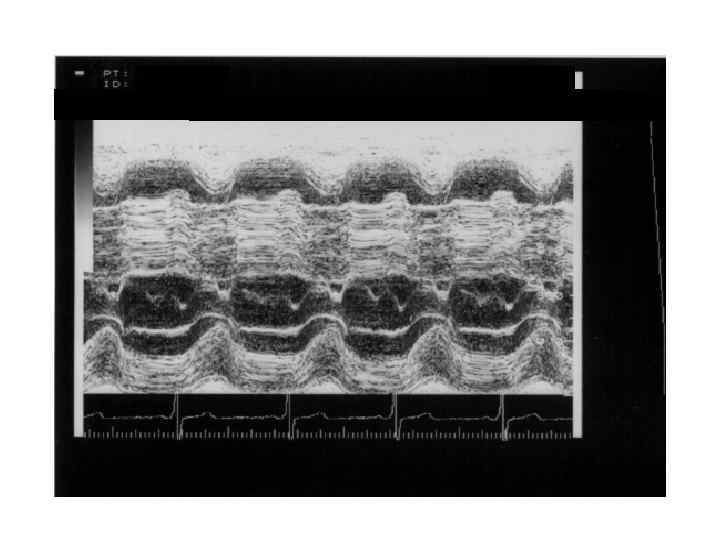

АДПЖ

АДПЖ